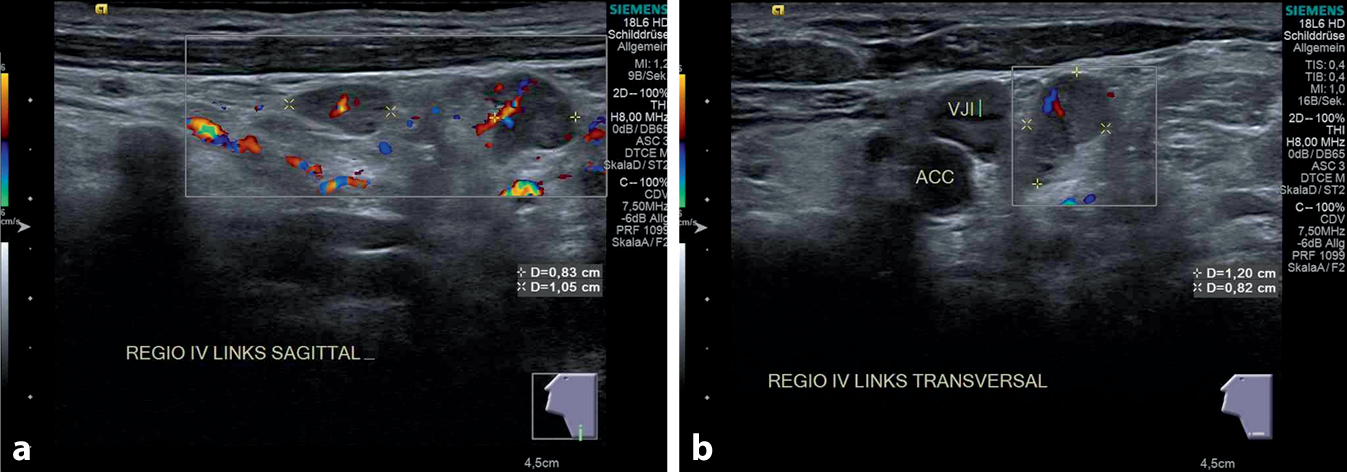

In der insgesamt blanden HNO-ärztlichen Routineuntersuchung waren zervikal keine pathologischen Lymphknoten palpabel. In der B‑Bild-Sonographie (Abb. 2) konnten in Region IV/V links 2 inhomogene lymphknotenähnliche Strukturen, rundlich konfiguriert mit einem maximalen Durchmesser von 1,2 cm, jeweils mit einem Solbiati-Index < 2, aber erhaltenem hilären Perfusionsmuster, dargestellt werden.

Abb. 2

Halsweichteilsonographie eines 75-jährigen Patienten mit 2 inhomogenen Lymphknoten, der größere mit einer Metrik von 1,20 × 0,82 × 0,83 cm links in Region IV, jeweils sagittal (a) und transversal (b). Mitabgebildet ansonsten unauffällige Halsweichteile